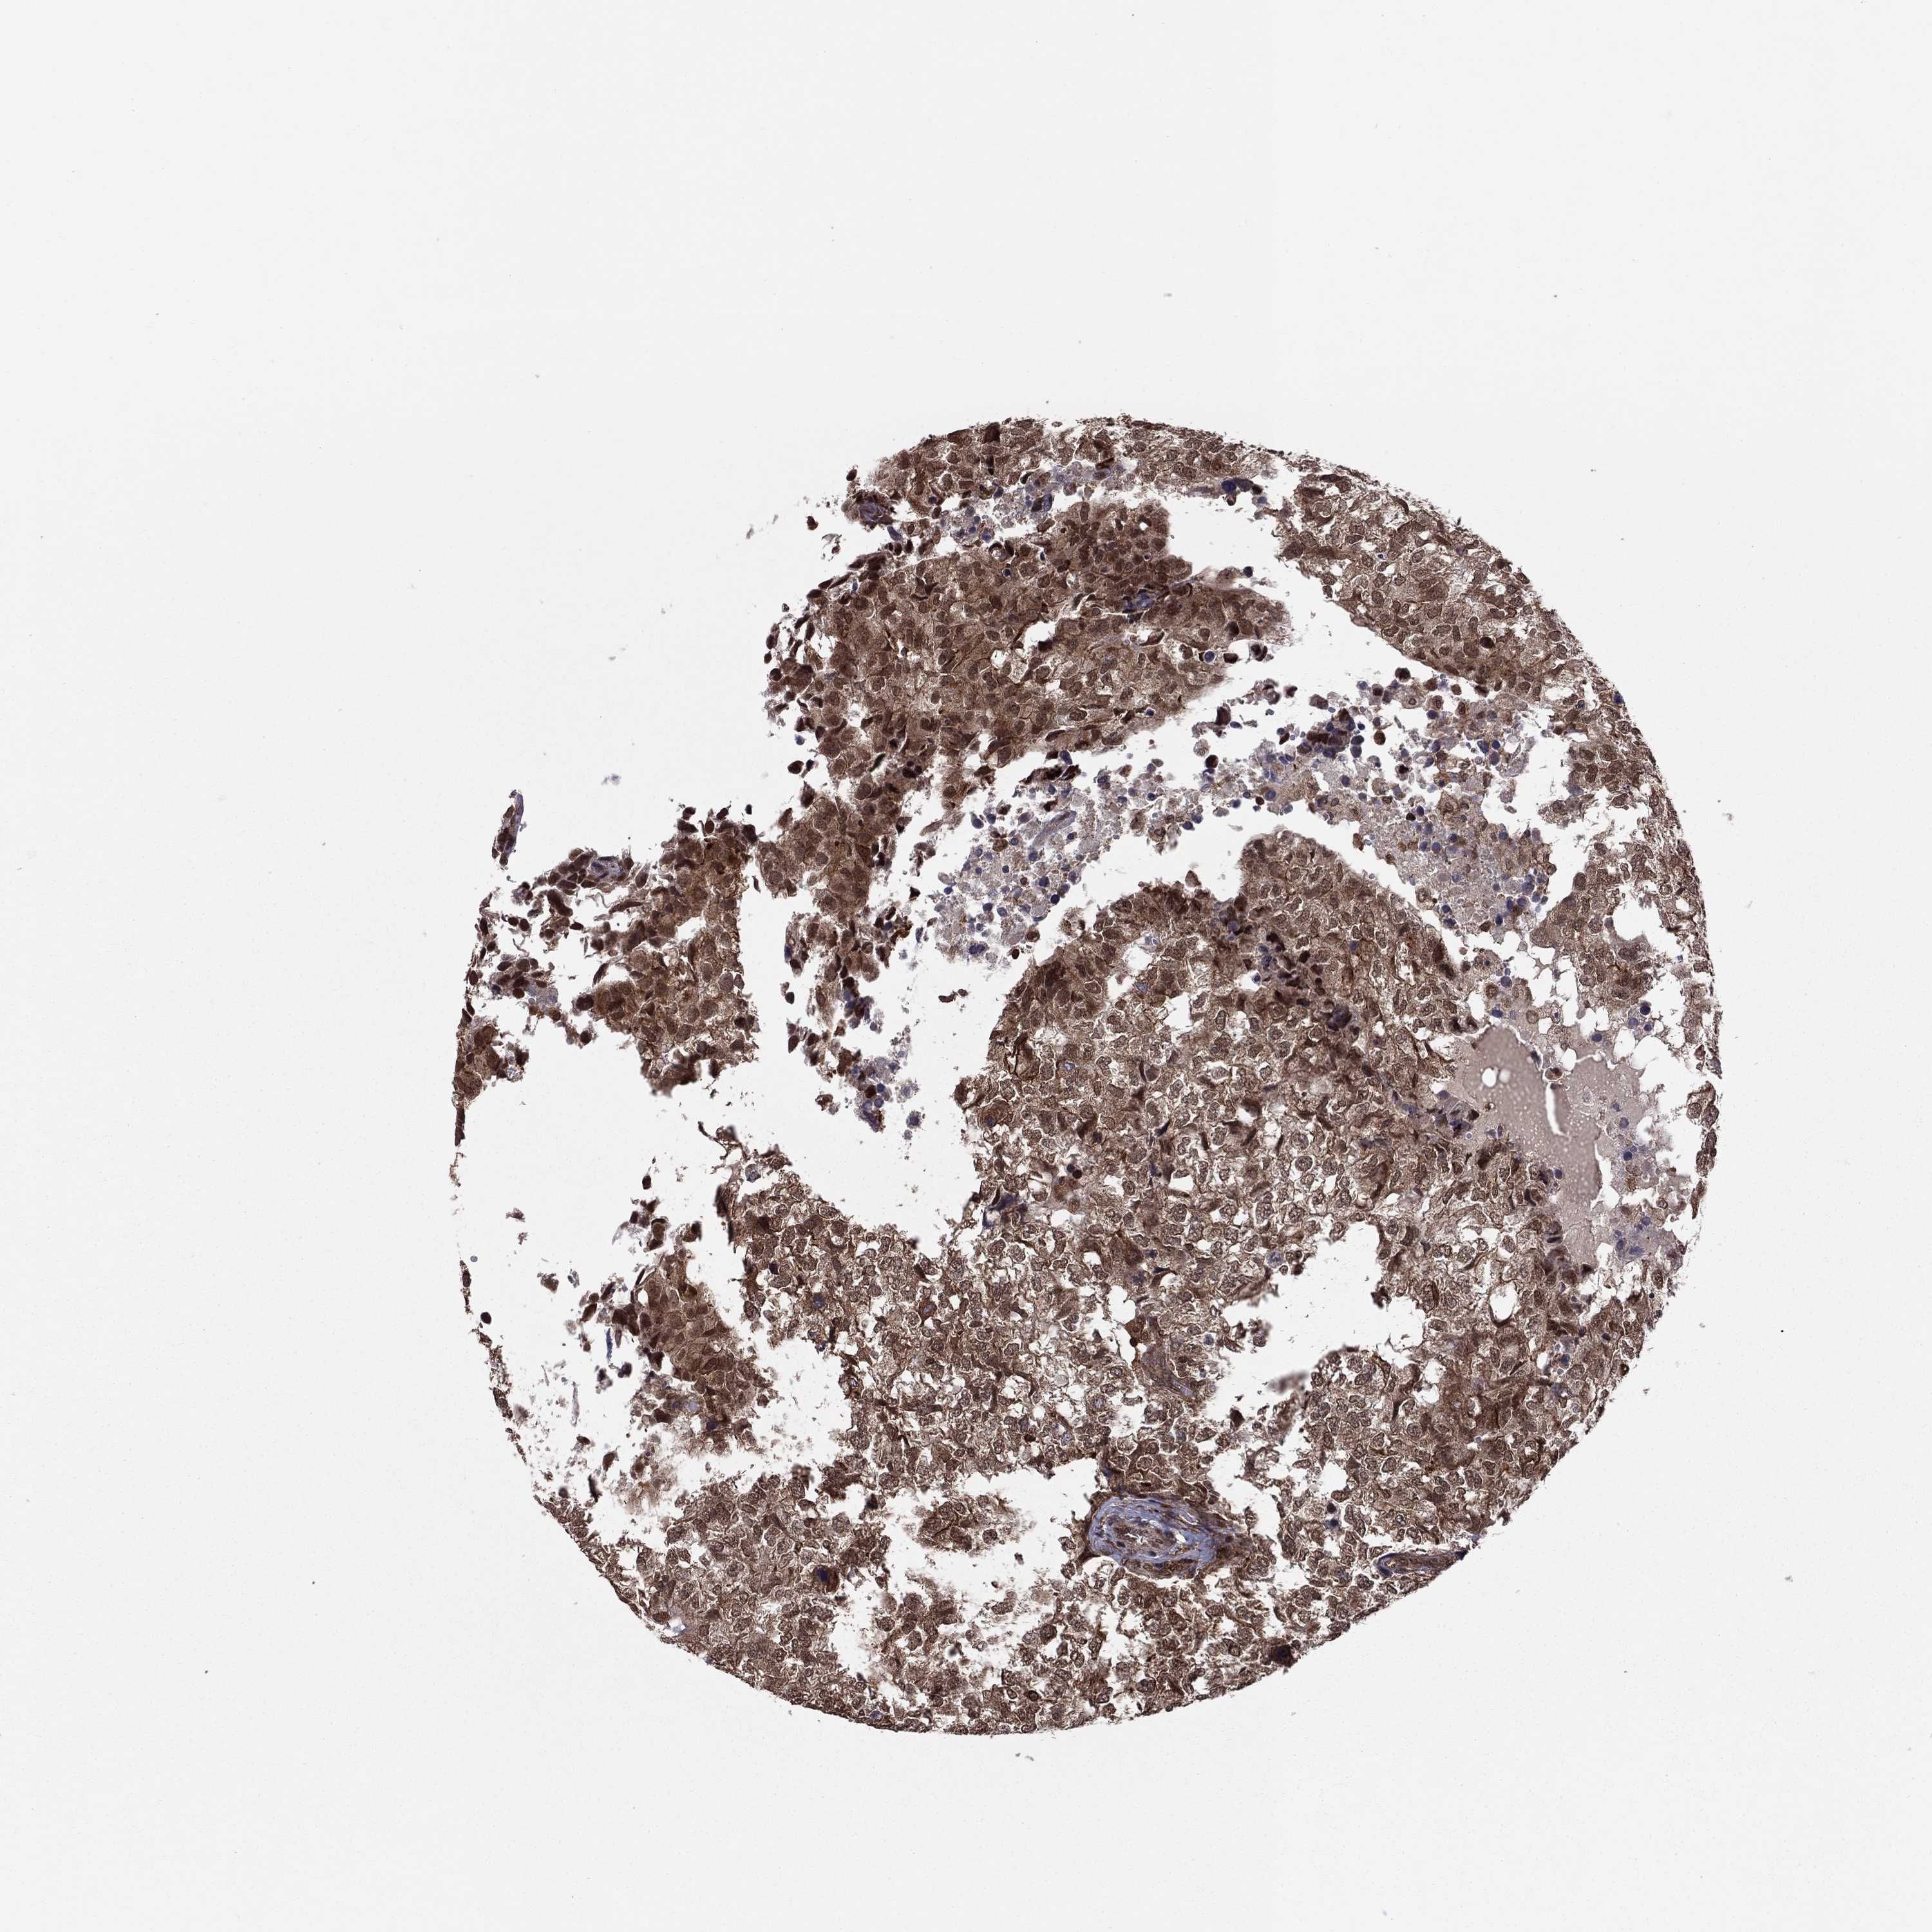

CANCER BREAST CANCER Show tissue menu

BRCA TCGA BRCA VALIDATION PROTEIN EXPRESSION

Breast cancer

Human cancer

Breast invasive carcinoma